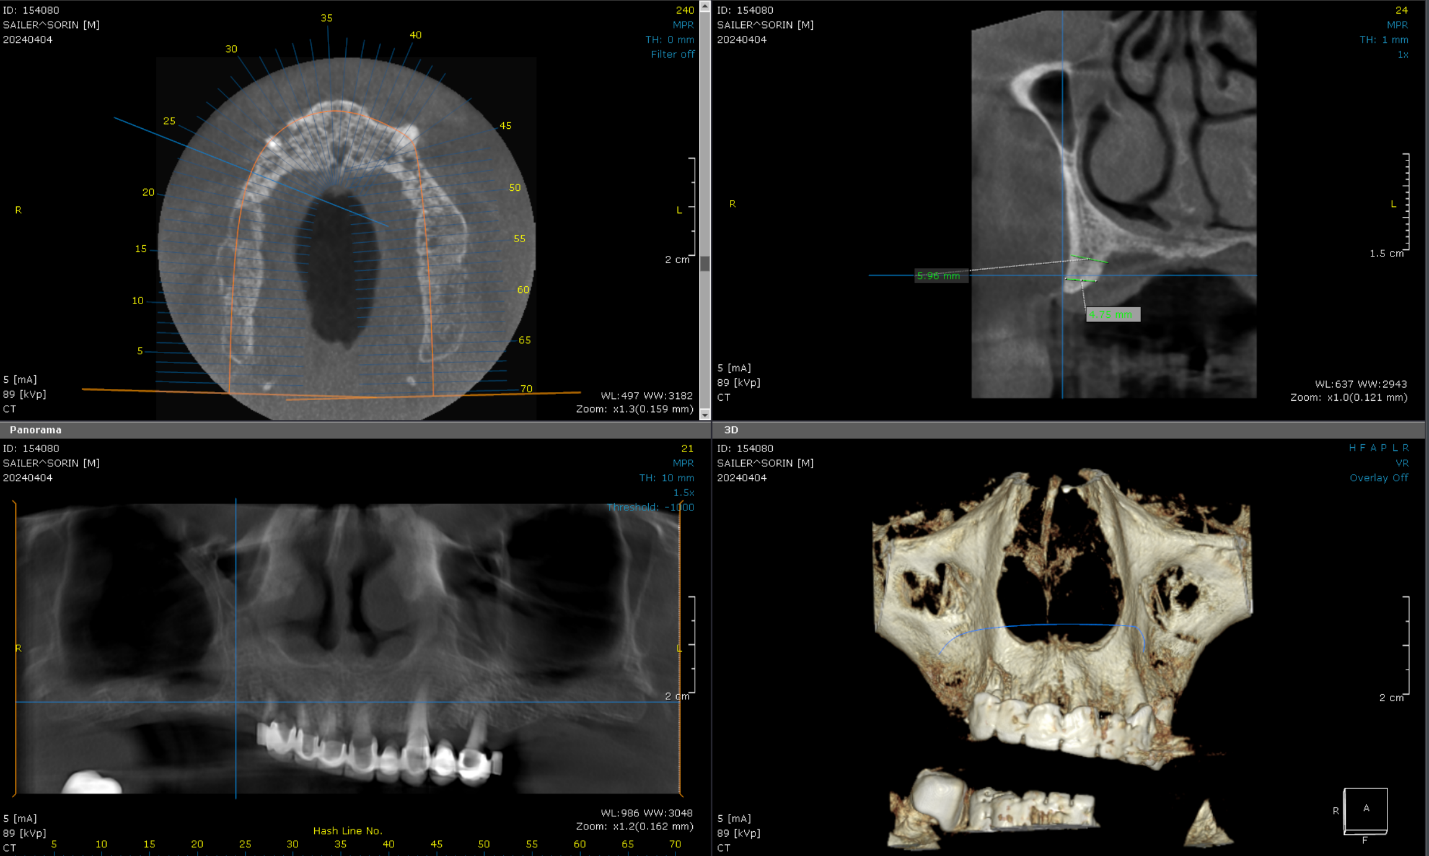

Cone Beam Computed Tomography (CBCT) scans were acquired for both the maxillary and mandibular arches. These scans provided critical insights into available bone volume, bone density, and anatomical considerations, forming a foundation for precise implant planning and guided surgery.

Patient had a new maxillary CT performed with the 2 dentures in occlusion.

Bone was measured to asses the amount of bone gained and the density of the said bone and also a first simulation of implant placement was performed.

Another view of the post graft healing in the mandibular arch and visibility of the composite marker additions done on the upper denture for alignment purposes between scan image and CBCT datasets.